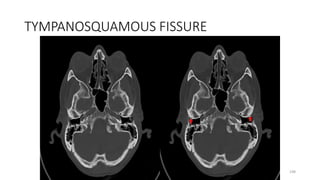

TYMPANO SQUAMOUS FISSURE

TYMPANOSQUAMOUS FISSURE